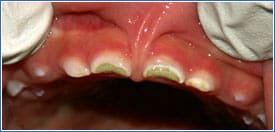

ECC affects teeth that emerge early and are least protected by saliva. Visualize a child sucking a bottle. With the child's tongue thrust forward, the maxillary incisors get maximal sugar exposure.

Typically ECC progresses in the following order:

• Upper incisors (maxillary anterior teeth)

• First molars

• Second molars

Mandibular incisors, despite emerging first, are generally less affected because they are protected by the tongue and pooling of saliva in that area.